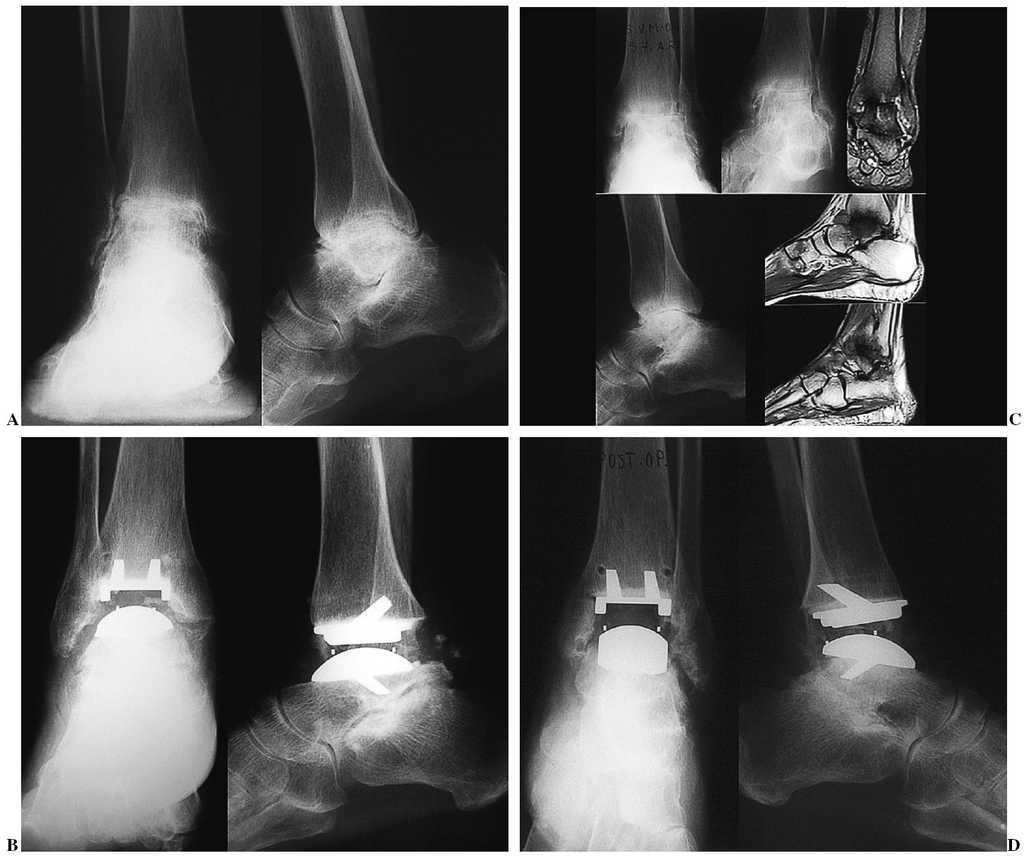

Recientemente hemos intervenido un caso excepcional, que sin duda puede abrir el camino para ampliar las indicaciones: el rescate de una anquilosis de tobillo por fracaso de una artrodesis, en una paciente de 41 años, que presentaba secuelas de un pie equinovaro congénito varias veces intervenido (fig. 8). La mejoría funcional y clínica que hemos observado nos hace ver con optimismo el futuro de esta indicación.

Figura 8. Indicación excepcional. Paciente de 41 años con secuelas de un pie equinovaro congénito. Artrodesis fallida de tobillo. Anquilosis dolorosa. Grados de movilidad: 10°. Radiografías preoperatorias anteroposterior (A) y lateral (B). Control postoperatorio: radiografía anteroposterior (C) y lateral (D). Arco de movilidad de 40°, no doloroso.